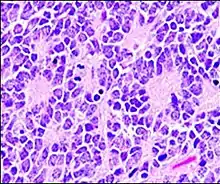

Micrograph of Homer Wright pseudorosettes

A Homer Wright pseudorosette is a type of pseudorosette in which differentiated tumor cells surround the neuropil.[15] Examples of tumors containing these are neuroblastoma, medulloblastoma, pinealoblastoma, and primitive neuroectodermal tumors of bone. Homer Wright rosettes are considered "pseudo" in the sense that they are not true rosettes. True rosettes are Flexner–Wintersteiner rosette, which contain an empty lumen. Homer Wright rosettes contain abundant fibrillary material. They are named for James Homer Wright.